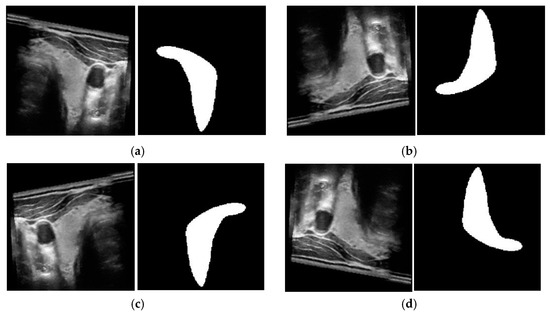

4.1. Experimental Datasets

4.2.2. Data Augmentation